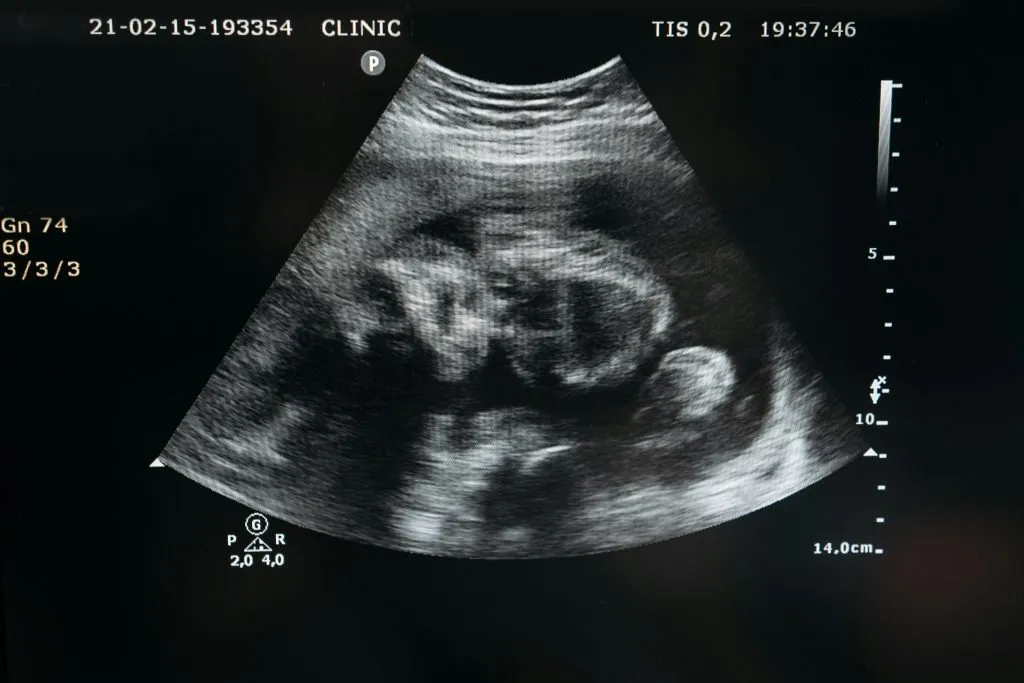

Пункцию яичников проводят через 34–36 часов после укола ХГЧ. Пациентке вводят общий короткий наркоз или седацию. Через влагалище под контролем УЗИ вводят специальную иглу, с помощью которой производят пункцию фолликулов и аспирацию их содержимого. Фолликулярную жидкость отправляют в лабораторию, где эмбриолог отбирает ооцит-кумулюсные комплексы.